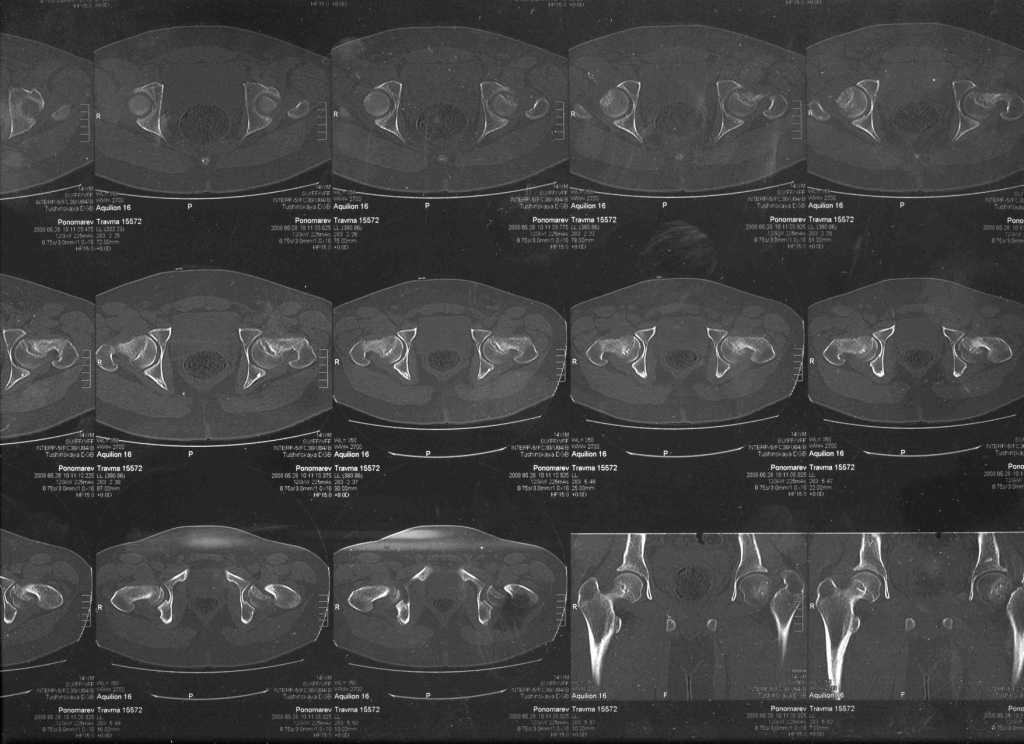

Госпитализирован ребёнок 14 лет. Мальчик, мягко говоря, крупный, гиперстенического типа сложения, ближе к десантнику. Весит 95 кг. Ожирение 2-й степени. Со слов больного - испытывает дискомфорт в области тазобедренного сустава в течение 3-х месяцев. На рентгенограммах - положение дел на момент поступления - конец мая. Укорочение конечности на 1,5 см. Ограничение внутренней ротации. Ходит, едва заметно прихрамывая на больную ногу. Эндокринологический статус находится в стадии обследования. Выполнена рентгенография в стандартных укладках, спиральная КТГ. Ясное дело, головка бедра <ушла> вниз и кзади. Пытающаяся <поймать> её шейка варизировалась и исполнила ретроверсию, создав изгиб во фронтальной плоскости. На рентгеноскопии - подвижность головки не определяется. Мальчик имеет далеко идущие планы на обустройство собственной жизни и образование. Крайне негативно относится к длительной иммобилизации и консервативному лечению. Загодя не согласен со снижением качества жизни в процессе лечения. Мнения коллег относительно дальнейшего лечения разделились. Успешность репозиции головки под наркозом - сомнительная в связи с имеющейся деформацией шейки бедра. Одни склоняются к тактике невмешательства - разгрузка больной конечности, ФЗТ , массаж, и т.д. Предлагают ждать завершения процесса <сползания> головки в условиях полной разгрузки, <тянуть> сустав до эндопротезирования как можно дольше. Другая группа коллег предлагает немедленную стабилизацию головки, что, кажется, правильно. Принимая во внимание анатомическое соотношение головки и шейки бедра, способ остеосинтеза так же вызвал массу споров, не приведших к единому и окончательному мнению. Пока дискуссия остановилась на стабилизации спицами Бека под контролем ЭОП, возможно с применением электродов для проведения электростимуляции слабыми импульсными токами. Техника проведения спиц, однозначно, будет сопряжена с техническими трудностями, обусловленными имеющейся деформацией шейки. Как бы Вы поступили, коллеги, в данной ситуации? Заранее спасибо. И прошу прощения за качество спимков. Буду отправлять их по очереди.